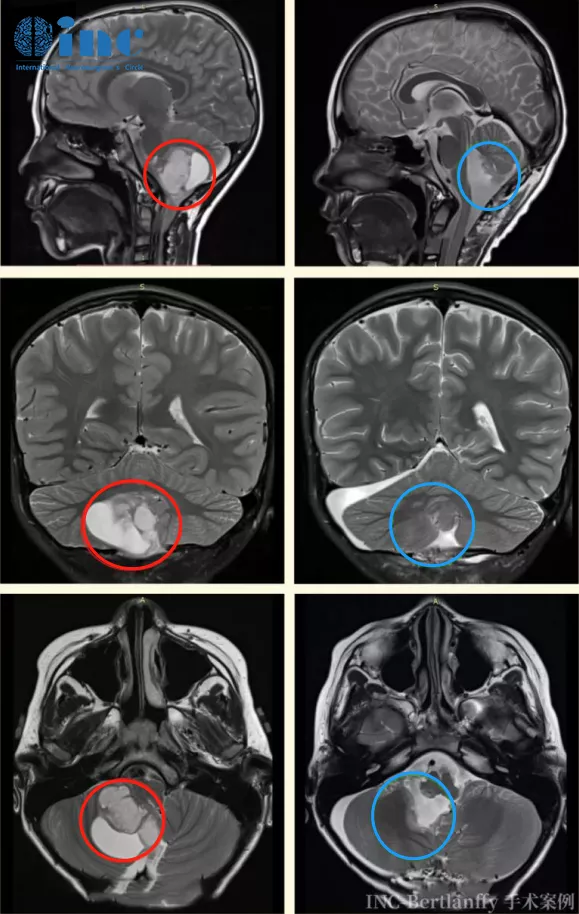

辰辰的术前术后MRI对比显示胶质瘤得到全切(左侧为术前,右侧为术后)